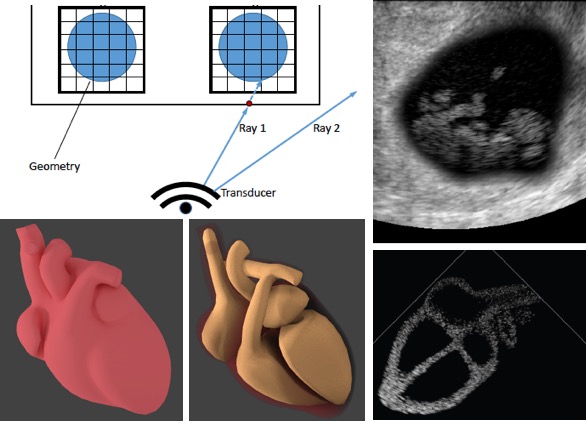

[2021] Lin Zhang, Tiziano Portenier, and Orcun Goksel:

"Learning Ultrasound Rendering from Cross-Sectional Model Slices for Simulated Training",

International Journal of Computer Assisted Radiology and Surgery 16:721-730, Apr 2021.

[2021] Lin Zhang, Tiziano Portenier, and Orcun Goksel:

"Learning Ultrasound Rendering from Cross-Sectional Model Slices for Simulated Training",

International Journal of Computer Assisted Radiology and Surgery 16:721-730, Apr 2021.

[2019] Rastislav Starkov, Christine Tanner, Michael Bajka, and Orcun Goksel:

"Ultrasound Simulation with Animated Anatomical Models and On-the-Fly Fusion with Real Images via Path Tracing",

Computers & Graphics 82:44-52, May 2019.

[2019] Rastislav Starkov, Christine Tanner, Michael Bajka, and Orcun Goksel:

"Ultrasound Simulation with Animated Anatomical Models and On-the-Fly Fusion with Real Images via Path Tracing",

Computers & Graphics 82:44-52, May 2019.

[2018] Oliver Mattausch, Maxim Makhinya, and Orcun Goksel:

"Realistic Ultrasound Simulation of Complex Surface Models Using Interactive Monte-Carlo Path Tracing",

Computer Graphics Forum 37(1):202-213, Feb 2018.

[2018] Oliver Mattausch, Maxim Makhinya, and Orcun Goksel:

"Realistic Ultrasound Simulation of Complex Surface Models Using Interactive Monte-Carlo Path Tracing",

Computer Graphics Forum 37(1):202-213, Feb 2018.